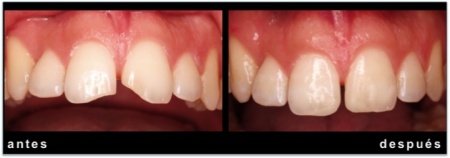

IMPLANTE EN INCISIVO LATERAL SUPERIOR POR AGENESIA